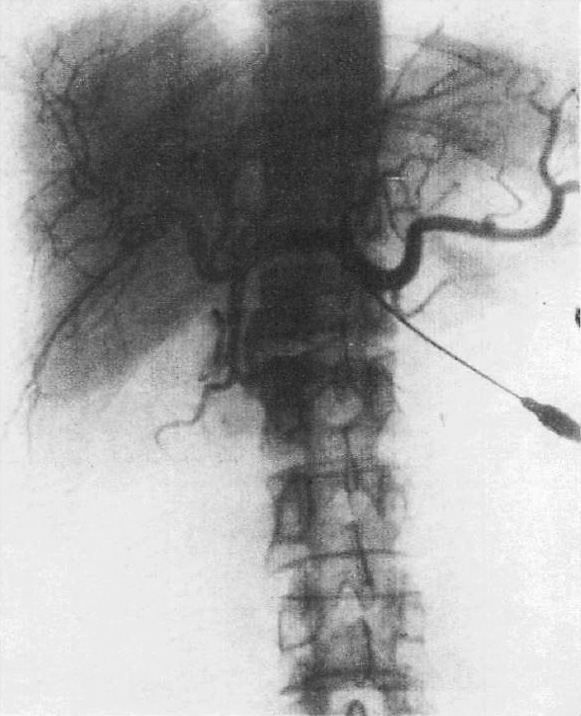

Seldinger SI. Acta Radiologica (Stockholm) 39:368-376, 1953

現在も血管造影手技の基本中の基本であるSeldinger法の報告文.この3年前にPeirceらが,それまでのゴム製泌尿器検査カテーテルにかえて細い壁薄のポリエチレン製カテーテルを導入したが,それでも穿刺針の中にカテーテルを通すにはかなり太い針による穿刺が必要で,カットダウンが必要があった(Peirce EC. Surg Gyn Obst 93:56-74,1951).Seldingerはガイドワイヤを使うことにより,カテーテルより細い針による経皮的穿刺を可能とし,カテーテルを安全確実に血管内に挿入する方法を開発した.これなくしてその後の血管造影,さらにはインターベンショナルラジオロジーの発展はなかったといえる画期的論文であるが,そのあまりに実際的な内容から学位論文には不適とされ,結局Seldingerはこの手技を経皮経肝胆管造影(PTC)に応用した論文で学位を得た.

前掲のSeldingerが使用したポリエチレンカテーテルはX線透過性であったため,透視下に位置を確認するには少量の造影剤を使用する必要があった.Seldingerの同僚放射線科医Ödmanは,X線不透過性のカテーテルを開発するとともに,ポリエチレンの可塑性を利用して目的とする血管に応じた形にカテーテルを成型し,大動脈一次分枝への選択的挿入を可能とした.これによって,経皮的血管造影の基本的技術がほぼ確立した.なおX線不透過カテーテルの詳細についてはここには書かれていないが,後年の記述によるとこの論文発表当時はバリウムを混入した素材を使っていたが,X線濃度が不充分なため,その後は酸化鉛など金属塩を使用して良い結果を得ている(Ödman P. Acta Radiol 52:152-64,1959).